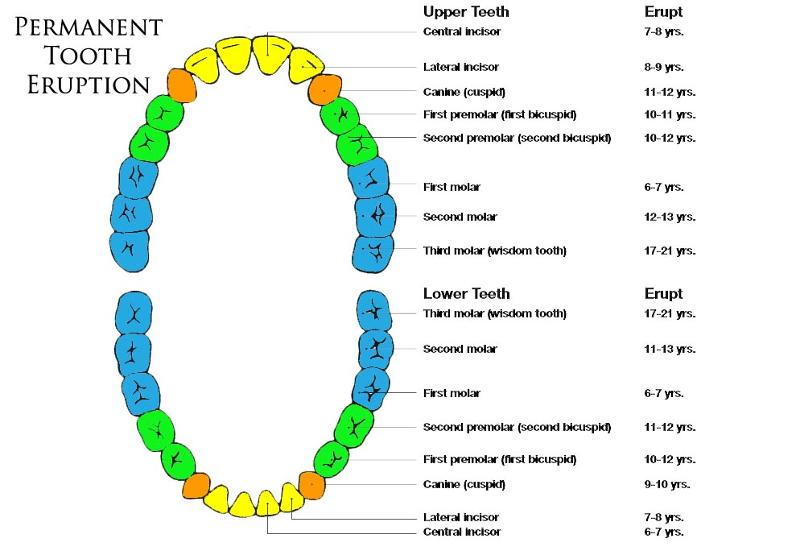

Deciduous Teeth

baby teeth

14

Permanent Teeth

Incisors (8)

Permanent Teeth FRONT

16

Canines (4)

Permanent Teeth

17

Premolars (8)

Permanent Teeth

18

Molars (12)

Permanent Teeth